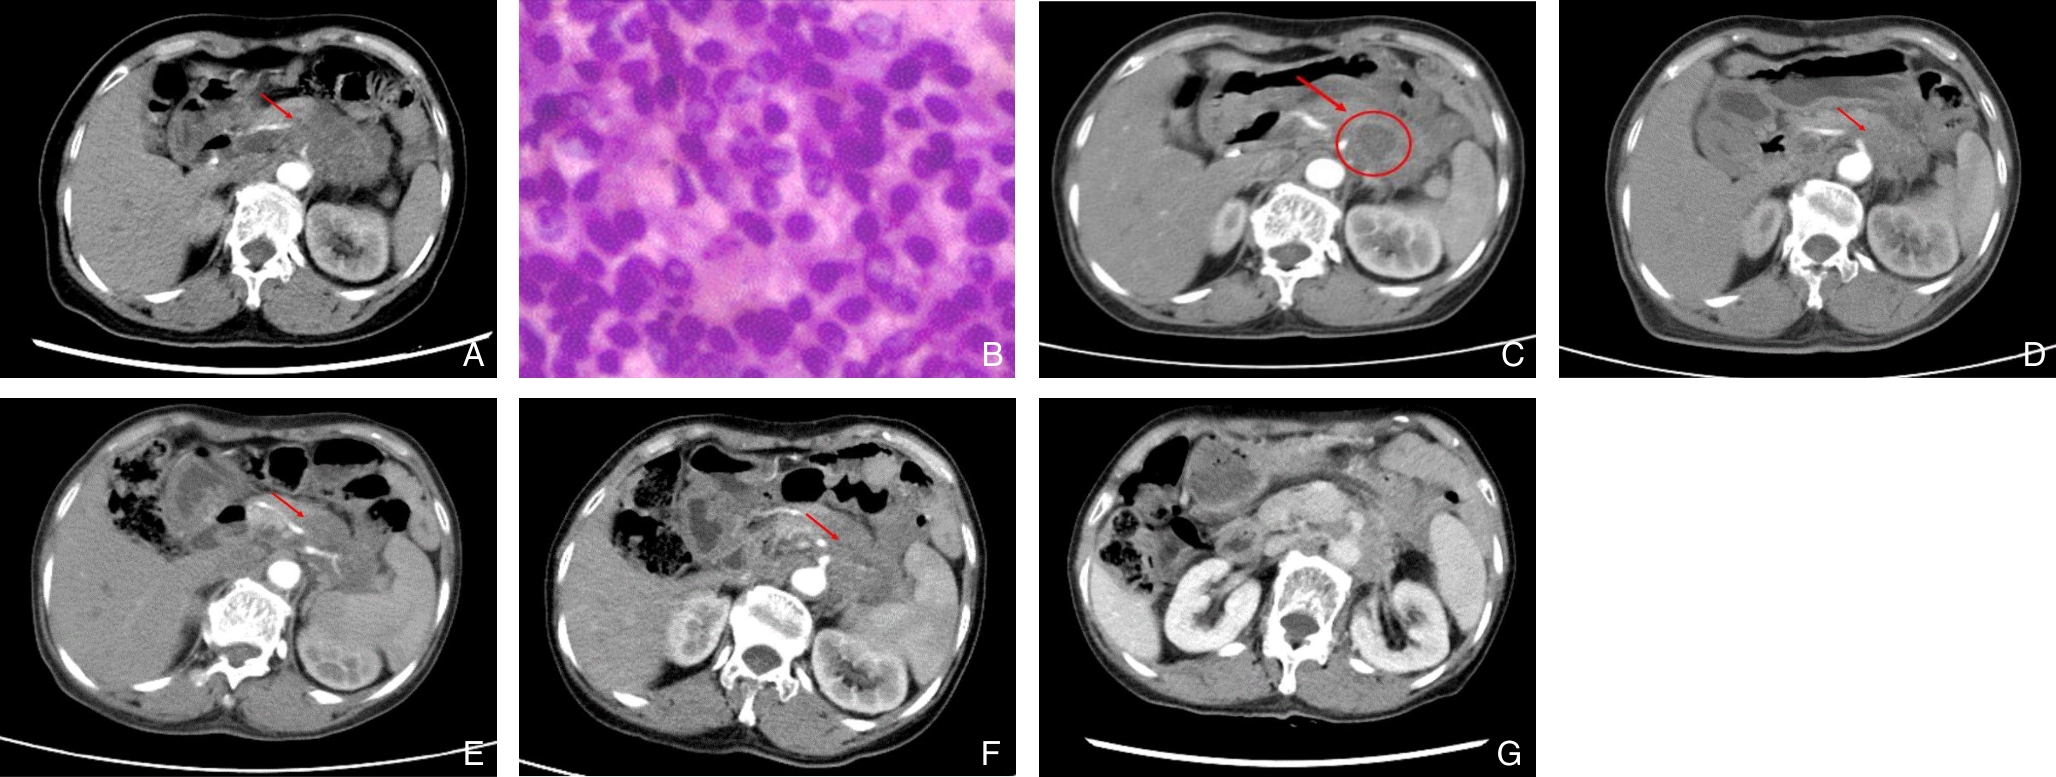

刘柏岐,申鼎成,宁彩虹,林嘉晏,孙泽芳,洪晓悦,朱帅,陈璐,李嘉荣,黄耿文

2025, 34(9):1902-1908. doi: 10.7659/j.issn.1005-6947.250123

摘要:背景与目的 早发广泛性气肿型胰腺炎(EP)是一种起病急骤、进展迅速、病死率极高的感染性胰腺坏死(IPN)亚型,临床少见,相关研究有限。本研究旨在分析其临床特征、病原谱特点、治疗方式及预后,为早期识别与干预提供依据。方法 回顾性分析2010年1月—2023年10月中南大学湘雅医院305例IPN患者的临床资料。根据影像学特征筛选出起病2周内胰腺或胰周坏死面积≥50%、呈大片状气泡征的早发广泛性EP 8例,并与普通IPN患者进行比较,分析两组的临床特征、病原学分布、治疗策略及结局。结果 305例IPN中,早发广泛性EP占2.6%。早发广泛性EP组病死率和多器官衰竭发生率均明显高于普通IPN组(75.0% vs. 24.6%、75.0% vs. 34.7%,均P<0.05)。早发广泛性EP患者共检出15株病原微生物,主要为肺炎克雷伯菌(62.5%)和大肠埃希菌(37.5%),其中耐碳青霉烯类肠杆菌感染率明显高于普通IPN组(75.0% vs. 31.1%,P=0.015)。治疗方式以经皮穿刺置管引流为基础的升阶梯策略为主,与普通IPN组无明显差异(P=0.625)。结论 早发广泛性EP是IPN的罕见亚型,具有进展迅速、病死率高的特点。肺炎克雷伯菌和大肠埃希菌是主要致病菌,应警惕其耐药感染风险。对疑似病例应尽早影像学评估并积极干预,以改善预后。